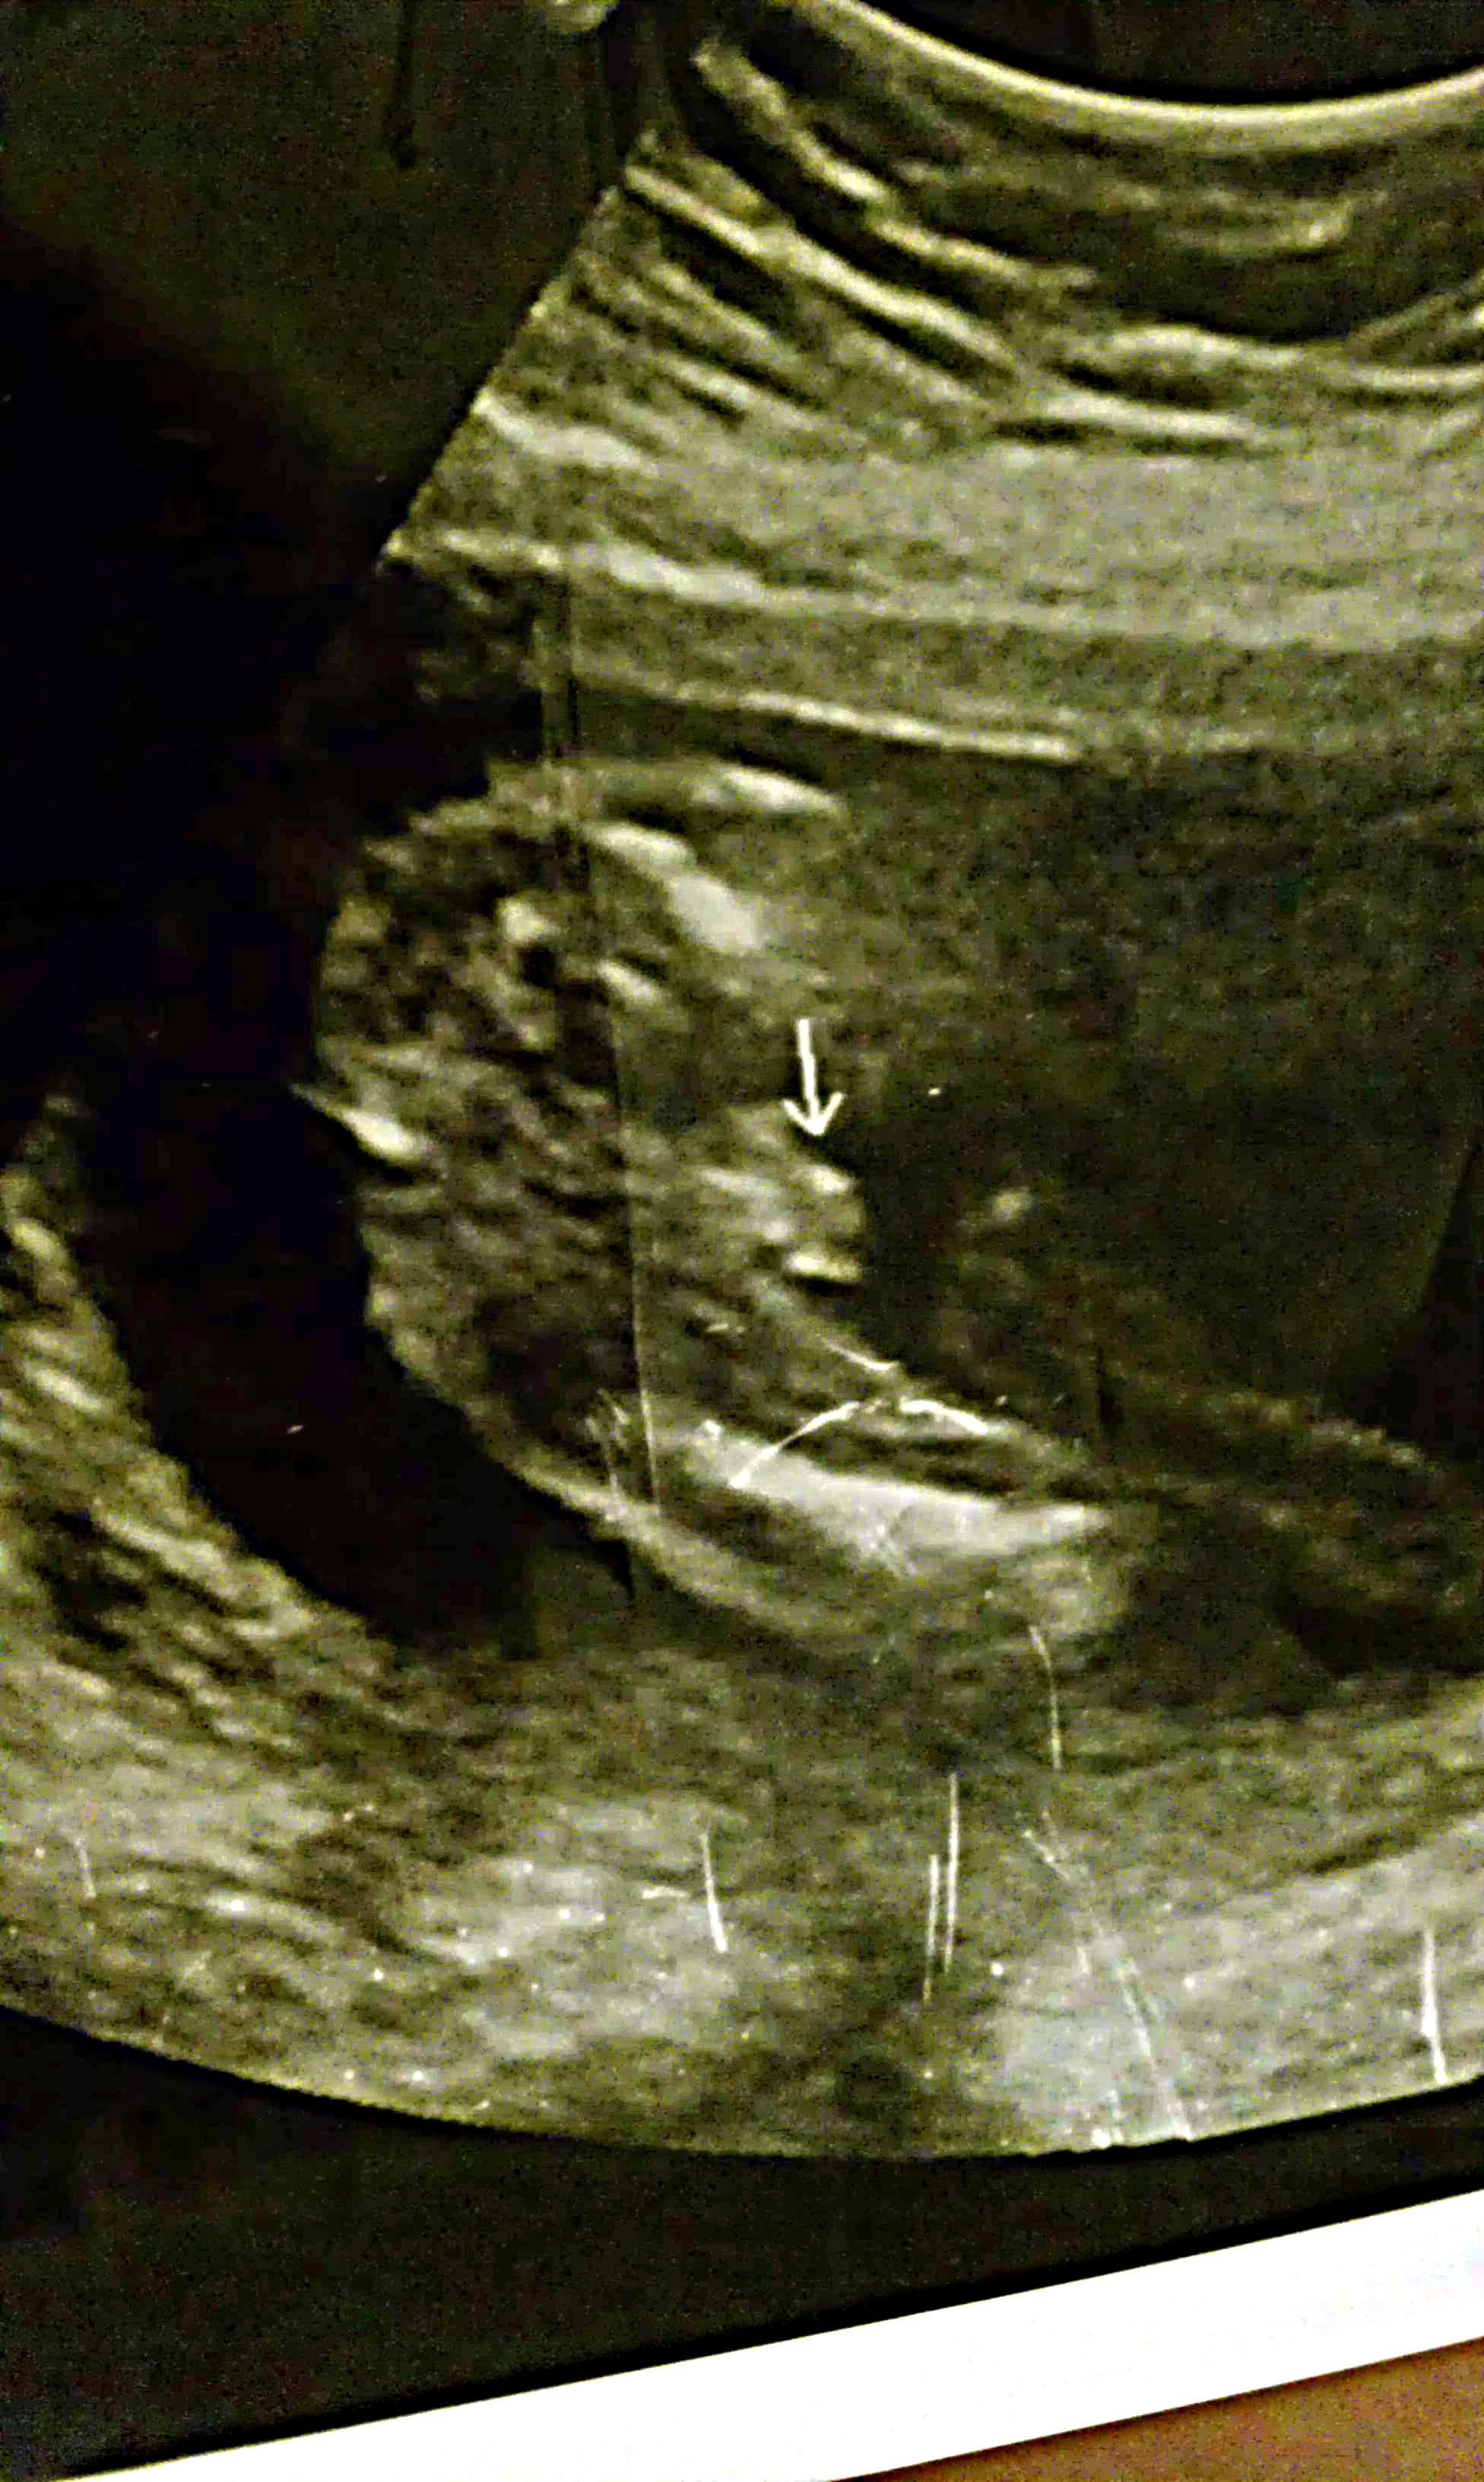

Unsure of Gender